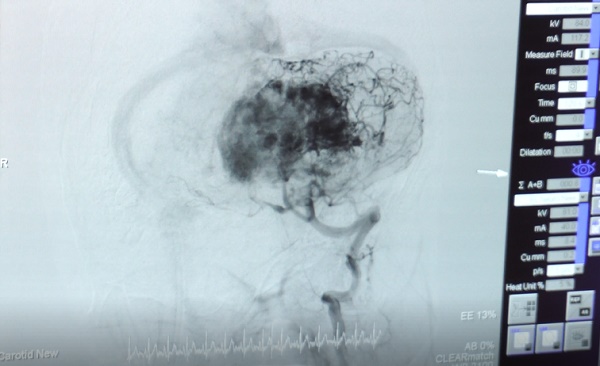

Theo Thạc sĩ, bác sĩ Trần Thị Mai Thy, Khoa Nội Thần Kinh Bệnh viện Quốc tế City, đột quỵ là bệnh lý tổn thương một phần cơ quan của não xảy ra đột ngột do mạch máu nuôi dưỡng bị tắc nghẽn hoặc vỡ. Khi thấy những tổn thương trên dây thần kinh số 7 biểu hiện là: miệng bị méo, chân tay bị yếu-liệt (bằng cách giơ hai cánh tay lên để xác định), nói chuyện không rõ tiếng, không nói được. Nếu có một trong 3 triệu chứng trên cần đưa người thân đến cấp cứu trong thời gian vàng.